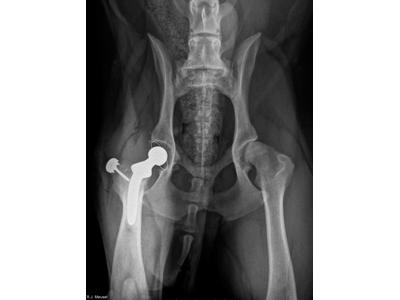

Provádíme operace páteře a hrudníku, wobbler, SLOT, totální endoprotézy, prasklé kolenní vazy, LCC, TPLO, TTA, dysplasie, TPO, trojité osteotomie pánve, JPS, diagnostiku kulhání, kožní onemocnění, perineální kýly, osteosyntézy, OCD. K dispozici máme vybavení jako RTG, USG, krevní analyzátory, atp.